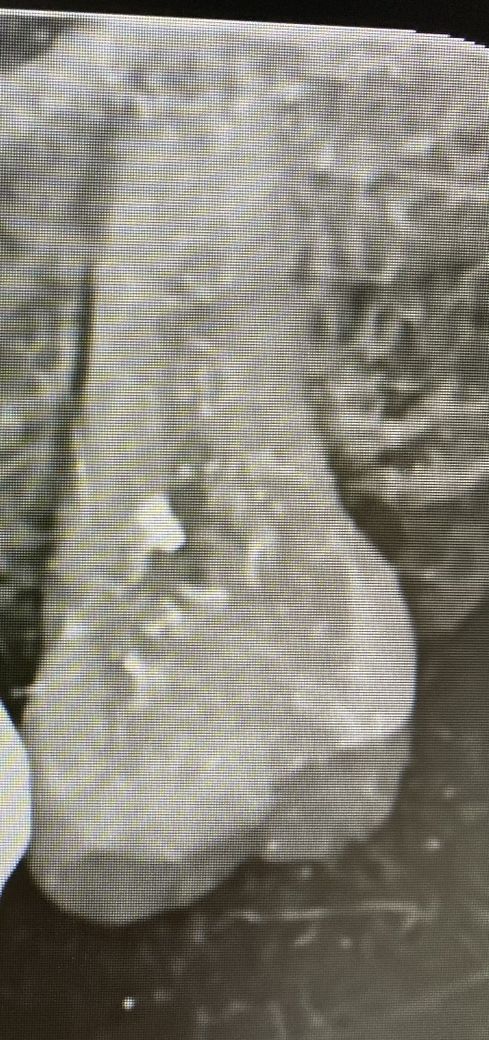

(제가 말씀드린 치아 엑스레이 사진입니다)

• 1번 째 사진

사진상으로 치주인대가 비후된것으로 보입니다. 하지만 잇몸뼈자체는 나쁘지 않아보입니다.